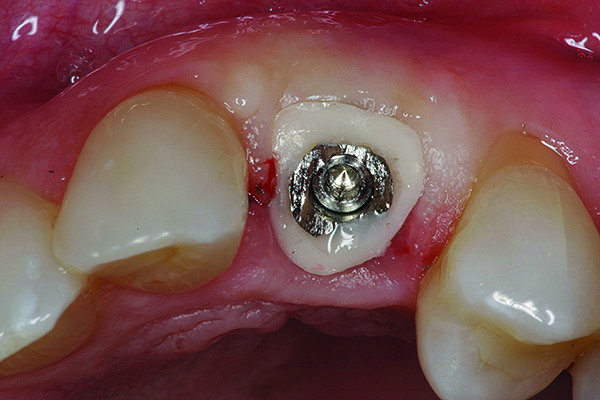

The cast used to fabricate the provisional as described above will work if the provisional was not altered. If it was altered, the screw-retained provisional is placed onto an analog and the analog is partially embedded in stone. (The clinician can stock a few embedded implant analogs of various sizes to expedite this process for future cases.) VPS bite registration material is then injected around the provisional covering the analog. Once set, the provisional is unscrewed, and a direct (open tray) transfer coping placed on the analog. Then, pattern resin (eg, GC Pattern Resin™, GC America, www.gcamerica.com) or flowable composite is flowed around the transfer coping, duplicating the cervical portion of the provisional. This transfer coping can be used to capture the orientation of the implant fixture as well as the soft tissue surrounding it. A radiograph should be taken to verify complete seating of the transfer coping prior to taking the impression, which will appear as shown in Figure 8.

Fig 9. Custom healing abutment in place, with blanching present upon insertion.

Figure 9